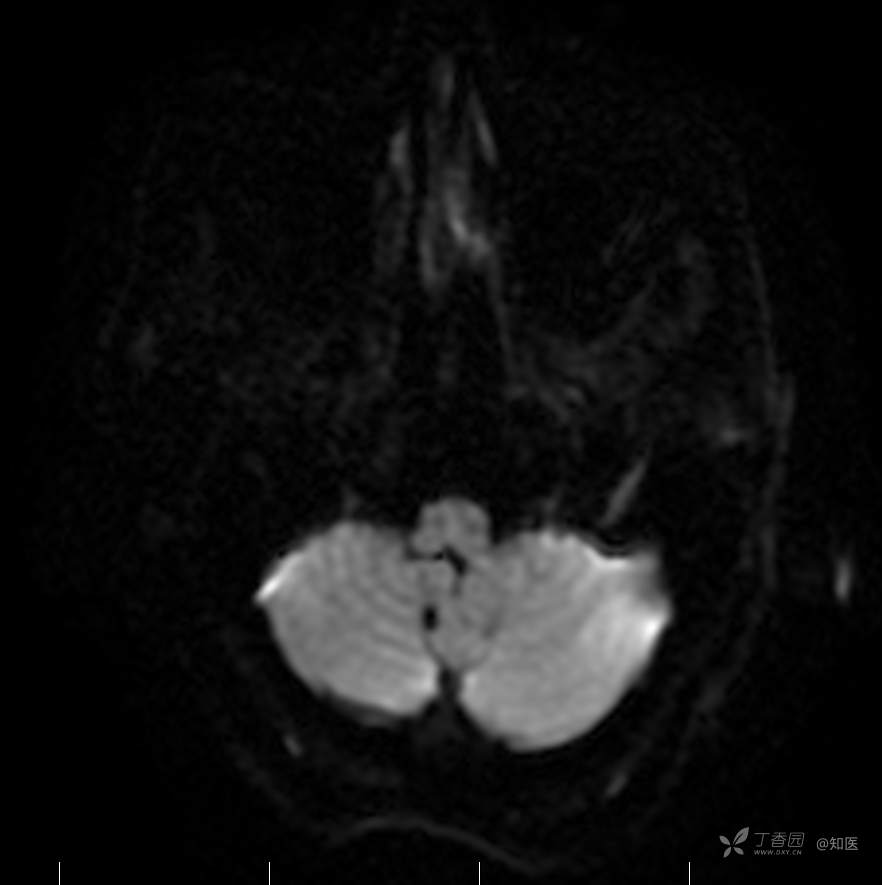

2021-6-15 DWI

2021-06-16日晨查房,患者自觉入院治疗后肢体无力症状较前稍改善,仍有活动后气短,余未诉特殊不适。ALSFRS-R评分:44分(单项均大于等于2分)。血压:123/63mmHg。神经系统查体:GCS 15分,右利手,查体合作,问答切题,粗测智能基本正常。额纹对称,双眼闭目紧,双侧瞳孔等大等圆,直径约3.0mm,对光反射灵敏,眼球运动自如,无眼震,双侧鼻唇沟对称等深,口角无歪斜。悬雍垂居中,双侧软腭抬举良好,咽反射灵敏、转颈、耸肩均一致有力。颈屈肌、颈伸肌力量5级。伸舌居中,无舌肌纤颤及萎缩。双侧岗上肌、岗下肌可见萎缩;双侧三角肌可见偶发肉跳、肌力5级,左侧肱二头肌肌力4+级、右侧4-级,双侧肱三头肌肌力4+级;双手握力可,双手大小鱼际肌及第一骨间肌可见萎缩,左侧明显,左侧手腕背伸力量4级、右侧4+级,双侧拇短展肌肌力4-级,双侧示指伸肌肌力3级,左侧指总伸肌肌力4级、右侧4-级,双侧小指展肌肌力4-级。双上肢肌张力对称减低。左侧肱二头肌反射迟钝、右侧未引出,双侧桡骨膜反射及肱三头肌反射未引出。左侧胸大肌反射阳性、右侧未引出,双侧Rossolimo征阳性、Hoffmann征阴性,下颌反射阴性。腹壁反射未引出。双下肢可见肌肉萎缩,以左侧明显;左侧髂腰肌肌力4级、右侧4-级,双侧股四头肌肌力5级,双足背伸力量3级,左足跖屈力量4级、右足4+级。双下肢肌张力对称基本正常。双侧膝腱反射、跟腱反射迟钝,双侧跖反射消失,双侧巴氏征未引出。右侧大腿外侧肌肉活检瘢痕周围浅感觉缺失,余肢体及躯干深浅感觉正常,共济运动对称正常。颈软,无抵抗,双侧布氏征及克氏征均阴性。辅助检查:微量元素(钙、镁、铁、铜、锌),微量元素测定(铅,镉)[复][2021-6-16 16:11:07]:钙1.19mmol/l;铁9.00mmol/L。急诊电解质七项[复][2021-6-16 10:41:41]:钾3.55mmol/L。血细胞分析+五分类[2021-6-16 9:57:17]:淋巴细胞百分比19.5%。[头颅,扩散成像(DWI)][头颅,磁敏感成像(SWI)][头颅,水抑制成像(FLAIR)][2021-6-16 18:10:50]:1.多发腔梗,脑白质脱髓鞘,脑萎缩。2.DWI:脑实质内未见明显高信号。3.磁敏感成像脑实质内未见明显异常信号灶。MMSE:26分(高中文化水平)。MoCA:23分。ADL评分:14分。ECAS评分:96分(ALS特异67分、ALS非特异29分)。肌电图:提示颈髓、腰髓、胸髓和延髓支配肌肉可见活动期神经源性损害,颈髓和腰髓支配肌肉同时可见慢性期神经源性损害;提示脊髓前角细胞损害可能,请结合临床。心电图大致正常。外送基因检查:TBK1基因杂合子,提示额颞叶痴呆和(或)肌萎缩性侧索硬化症4型。二线主治医师查看患者后示:1.患者基因检查结果显示TBK1基因杂合子,提示额颞叶痴呆和(或)肌萎缩侧索硬化症4型,结合外院影像学检查可见额颞叶萎缩明显,来院后复查头颅FLAIR+DWI+SWI亦提示脑萎缩,量表评估提示认知功能稍减退,ECAS评分基本正常。综上,修正诊断:肌萎缩侧索硬化症(ALS) 额颞叶变性 低钾血症 高血压2级(高危) 多发腔隙性脑梗死。因TBK1基因引起的额颞叶痴呆和(或)肌萎缩侧索硬化症为常染色体显性遗传,患者父亲已逝,母亲健在,诉无明显认知功能障碍或肌肉萎缩等表现,建议患者母亲抽血送检,进一步明确致病基因来源,必要时患者子女也可行基因检查进一步明确。2.患者目前诊断基本明确,根据文献报道,合并FTD的ALS患者整体生存周期较短(约19个月),目前患者发病已1年余,应充分与患者家属沟通病情,告知疾病预后及生存周期情况,同时建议开始口服利鲁唑片,延缓疾病进展。余治疗方案暂不予调整。密观病情变化,遵嘱执行。

2021-06-18出院总结: 卫某某,男,60岁,以“四肢僵硬1年,加重伴无力半年”之主诉入院。查体:生命体征平稳,心肺腹查体无明显异常。神经系统查体:GCS 15分,右利手,查体合作,问答切题,粗测智能基本正常。额纹对称,双眼闭目紧,双侧瞳孔等大等圆,直径约3.0mm,对光反射灵敏,眼球运动自如,无眼震,双侧鼻唇沟对称等深,口角无歪斜。悬雍垂居中,双侧软腭抬举良好,咽反射灵敏、转颈、耸肩均一致有力。颈屈肌、颈伸肌力量5级。伸舌居中,无舌肌纤颤及萎缩。左侧肱二头肌肌力4+级、右侧肱二头肌及双侧三角肌肱三头肌肌力5级;左手大小鱼际肌可见萎缩,左手握2指松、右手握力可,左手拇短展肌、示指伸肌、指总伸肌及抬腕力量3级,右手拇短展肌、示指伸肌、指总伸肌及抬腕力量4-级。双上肢肱二头肌反射、肱三头肌反射、桡骨膜反射均对称减低;双侧Hoffmann征、Rossolimo征、胸大肌反射及掌颏反射阴性,下颌反射阴性。双侧上、中、下腹壁反射可引出。左侧髂腰肌肌力4-级、右侧髂腰肌肌力4级,双侧股四头肌肌力5-级;右足背伸力量3级、左足背伸力量2级,双足跖屈力量5级。双下肢膝腱反射、跟腱反射对称减低;双侧膝阵挛、踝阵挛未引出。双侧巴氏征、Chaddock征均未引出。右侧大腿外侧肌肉活检处周围浅感觉减退,余四肢及躯干部深浅感觉正常,共济运动对称正常。颈软,无抵抗,双侧布氏征及克氏征均阴性。辅助检查:肌电图(2021-05-08,某军医大学附属医院):神经源性损害(颈段、腰骶段受累,胸段可疑;重复神经电刺激(低频、高频)可见左腋神经递减现象。 肌肉活检(2021-05-18,某军医大学附属医院):(右股四头肌)考虑神经源性损害,建议结合临床除外运动神经元病等。入院诊断:1.肢体无力:肌萎缩侧索硬化症(ALS);2.高血压1级(中危)。入院后查血清蛋白电泳:α2-球蛋白6.50%。凝血六项:血浆凝血酶原时间比值0.93;凝血酶原国际标准化比值0.93。贫血因子三项:维生素B12>1476.00pmol/L。平诊肝功十三项+平诊心肌酶谱五项+血同型半胱氨酸测定+平诊血脂八项+平诊肾功七项+平诊电解质八项:尿素3.05mmol/L;肌酐49umol/L;钾3.15mmol/L;高密度脂蛋白0.99mmol/L;载脂蛋白A1.131g/L;脂蛋白(a)333mg/L;肌酸激酶420U/L;总胆红素22.1umol/L;直接胆红素5.4umol/L。微量元素(钙、镁、铁、铜、锌),微量元素测定(铅,镉):钙1.19mmol/l;铁9.00mmol/L。急诊电解质七项:钾3.55mmol/L。血细胞分析+五分类:淋巴细胞百分比19.5%。[头颅,扩散成像(DWI)][头颅,磁敏感成像(SWI)][头颅,水抑制成像(FLAIR)]:1.多发腔梗,脑白质脱髓鞘,脑萎缩。2.DWI:脑实质内未见明显高信号。3.磁敏感成像脑实质内未见明显异常信号灶。MMSE:26分(高中文化水平)。MoCA:23分。ADL评分:14分。肌电图:提示颈髓、腰髓、胸髓和延髓支配肌肉可见活动期神经源性损害,颈髓和腰髓支配肌肉同时可见慢性期神经源性损害;提示脊髓前角细胞损害可能。血尿粪常规、免疫八项、风湿三项、血沉、传染指标、血同型半胱氨酸、糖化血红蛋白等未见明显异常。心电图、肺通气功能大致正常。住院期间给予营养神经、清除氧自由基等对症支持治疗。现患者诊断基本明确,生命体征平稳,一般情况良好,可予今日出院。出院诊断:1.肌萎缩侧索硬化症(ALS);2.额颞叶变性;3.低钾血症;4.高血压2级(高危);5.多发腔隙性脑梗死。出院医嘱:1.注意休息,加强营养,低盐、高蛋白高纤维素饮食,注意休息,适当锻炼,避免剧烈运动及重体力劳动。2.出院继续口服药物:甲钴胺 500ug/次,3次/日;辅酶Q10 10mg/次,3次/日;维生素E 100mg/次,2次/日;美金刚 10mg/次,1次/日;利鲁唑片,50mg/次,2次/日,与餐间隔1.5-2小时。3.出院继续用依达拉奉(必存)60mg+0.9%氯化钠 200ml,静滴,1次/日(首疗程14天,后每疗程10天,间隔20天,共使用6个疗程)。4.1月后门诊复查血常规、肝肾功能、电解质功能;3月后我科门诊再次复诊。5.不适随诊。